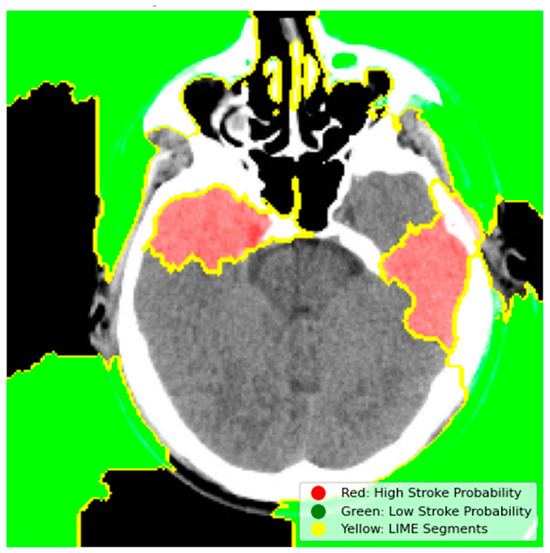

4.4. Stroke Prediction Visualization

4.6.1. Model Explainability Using LIME

- Red Regions (High Stroke Probability): These areas, highlighted in red, represent regions where the model detected features strongly associated with stroke, such as hyperdense hemorrhagic lesions or ischemic hypoperfusion. The red regions in the left hemisphere, for instance, correspond to the hyperdense clot, a key indicator of a hemorrhagic stroke.

- Green Regions (Low Stroke Probability): Green areas indicate regions with minimal influence on stroke prediction, typically healthy brain tissue or non-stroke-related anatomy.

- Yellow Outlines (LIME Segments): The image is divided into superpixels marked by yellow boundaries. LIME perturbs these segments to assess their impact on the model’s prediction. By masking and observing the changes in the prediction, LIME identifies the critical regions that drive the model’s decision-making process.